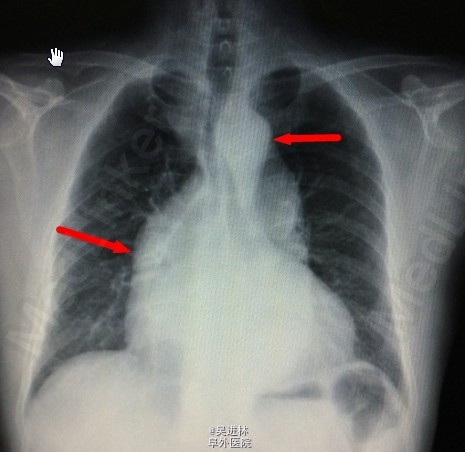

患者男,68岁,因“发现主动脉关闭不全11年”入院。患者11年前因头晕,就诊与当地医院,心脏超声提示:主动脉瓣关闭不全。后患者逐年复查,未行特殊治疗。1周前患者来我院就诊,超声提示:二叶瓣畸形,主动脉瓣重度狭窄办重度关闭不全,主动脉窦部及生主动脉增宽,未行手术入院。

诊断: 主动脉瓣二叶瓣畸形 主动脉关闭不全 主动脉窦部及生主动脉增宽 心脏扩大 心功II级 高血压病2级(极高危) 处理:手术换瓣bental

正常的主动脉瓣共有三个瓣膜。心脏收缩时,三个瓣膜同时打开,血液由左心室进入主动脉;心脏舒张时,三个瓣膜协同关闭,防止血液从主动脉返流入左心室。若主动脉瓣先天性只有两个瓣膜,称为主动脉瓣二瓣化畸形,是最常见的先天性主动脉瓣狭窄畸形。由于瓣叶结构异常,长期受到血流的不断冲击,易引起瓣膜增厚、钙化、僵硬、纤维化,最终导致瓣膜狭窄。这样会引起体循环灌注不足,头晕,乏力,心绞痛。更关键的,由于血流动力学改变,常常导致主动脉根部瘤样扩张。